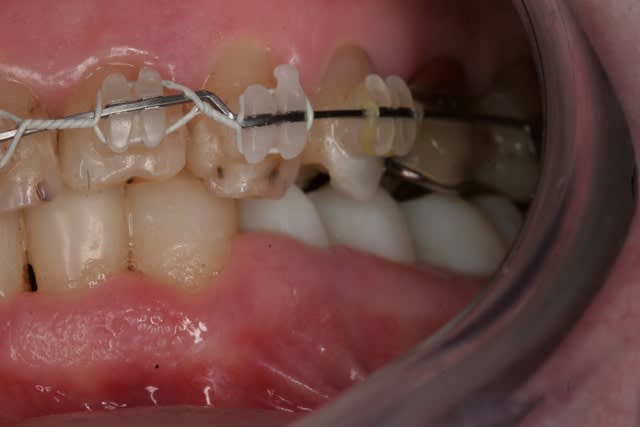

Donc la suite, évidement ortho: ingression du bloc incisivo canin sup avec ré alignement des arcades, extraction de la 14 nécessaire et ré alignement des milieux interincisif.

Pendant la finalisation du haut (axe mésio-disto incisif, à corriger à la fin pour faciliter gingivoplastie incisif sup). Il y a eu composite vestibulaire pelliculaire sous digue de 33 à 43, reprise soins et ancrage + provisoires 34,35, 36, 46; et composite sous digue 37 et 47.